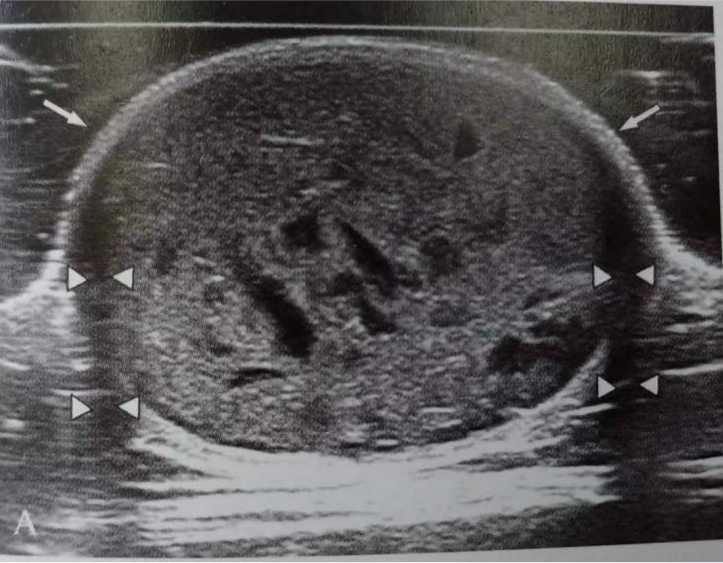

(4)評估皮膚惡性腫瘤的累及范圍及臨床分型分期

(含腫瘤厚度、周邊軟組織浸潤、皮膚附屬器累及、深部組織累及、淋巴結(jié)轉(zhuǎn)移、器官轉(zhuǎn)移等)。